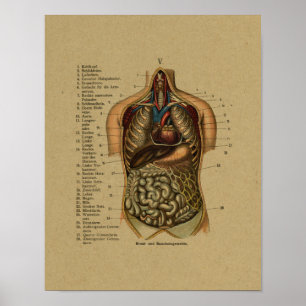

Impressão interno alemão da anatomia do vintage

Preço23,90 €